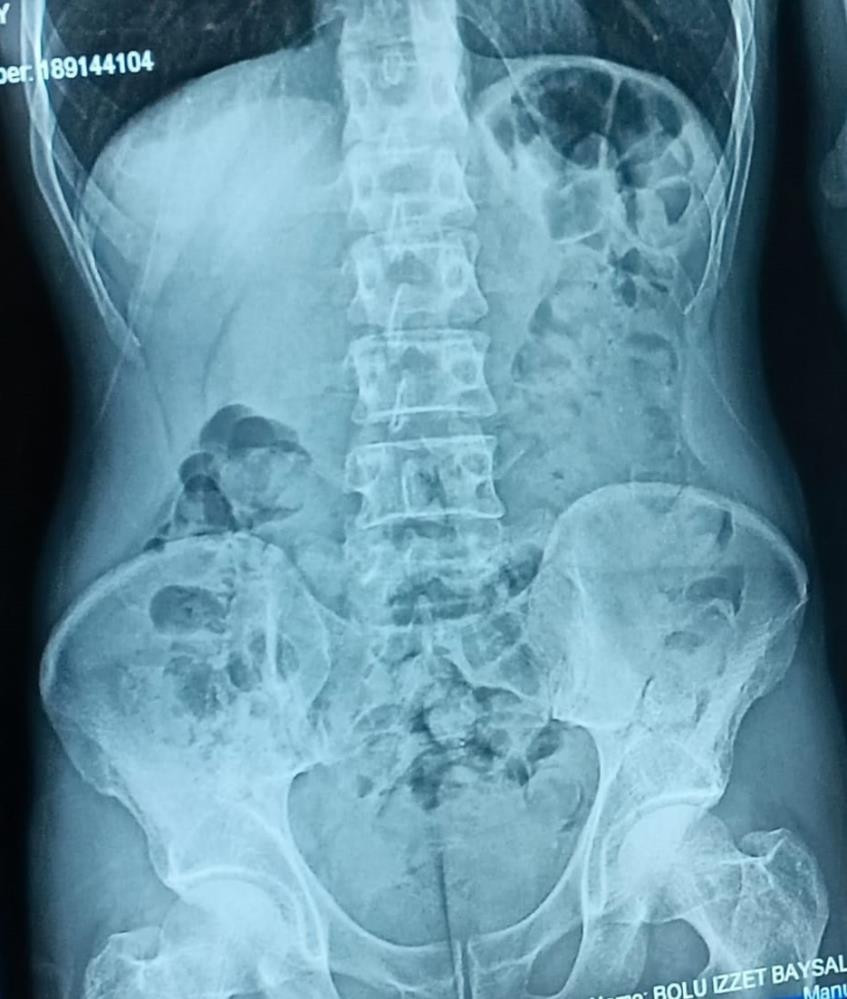

Yapılan sorgusunda midesinde kapsül halinde uyuşturucu madde olduğunu itiraf eden Şefik B., hastaneye götürülerek mide röntgeni çekildi. Röntgende midesinde çok sayıda kapsül tespit edilen Şefik B.’nin, 48 parça halinde 542 gram eroini doğal yollarla çıkarması sağlandı.